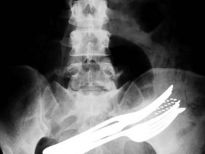

Bu röntgenler gerçek!

İki çatalı, bir tükenmez kalemi ve diş fırçasını yutmuş bir hasta.